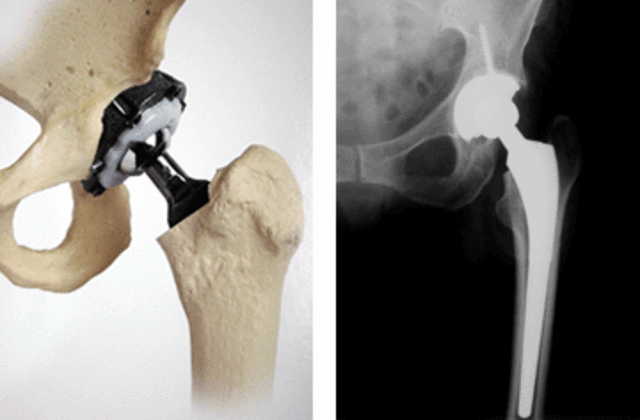

• Biomaterial - Protesis de cadera

Biomaterial - Protesis de cadera

Una protesis es un elemento artificial que se implanta en el cuerpo del paciente y que sustituye a una parte dañada del cuerpo del mismo, normalmente las prótesis están hechos de materiales resistentes, que no sean corrosivos y que el cuerpo los acepte.